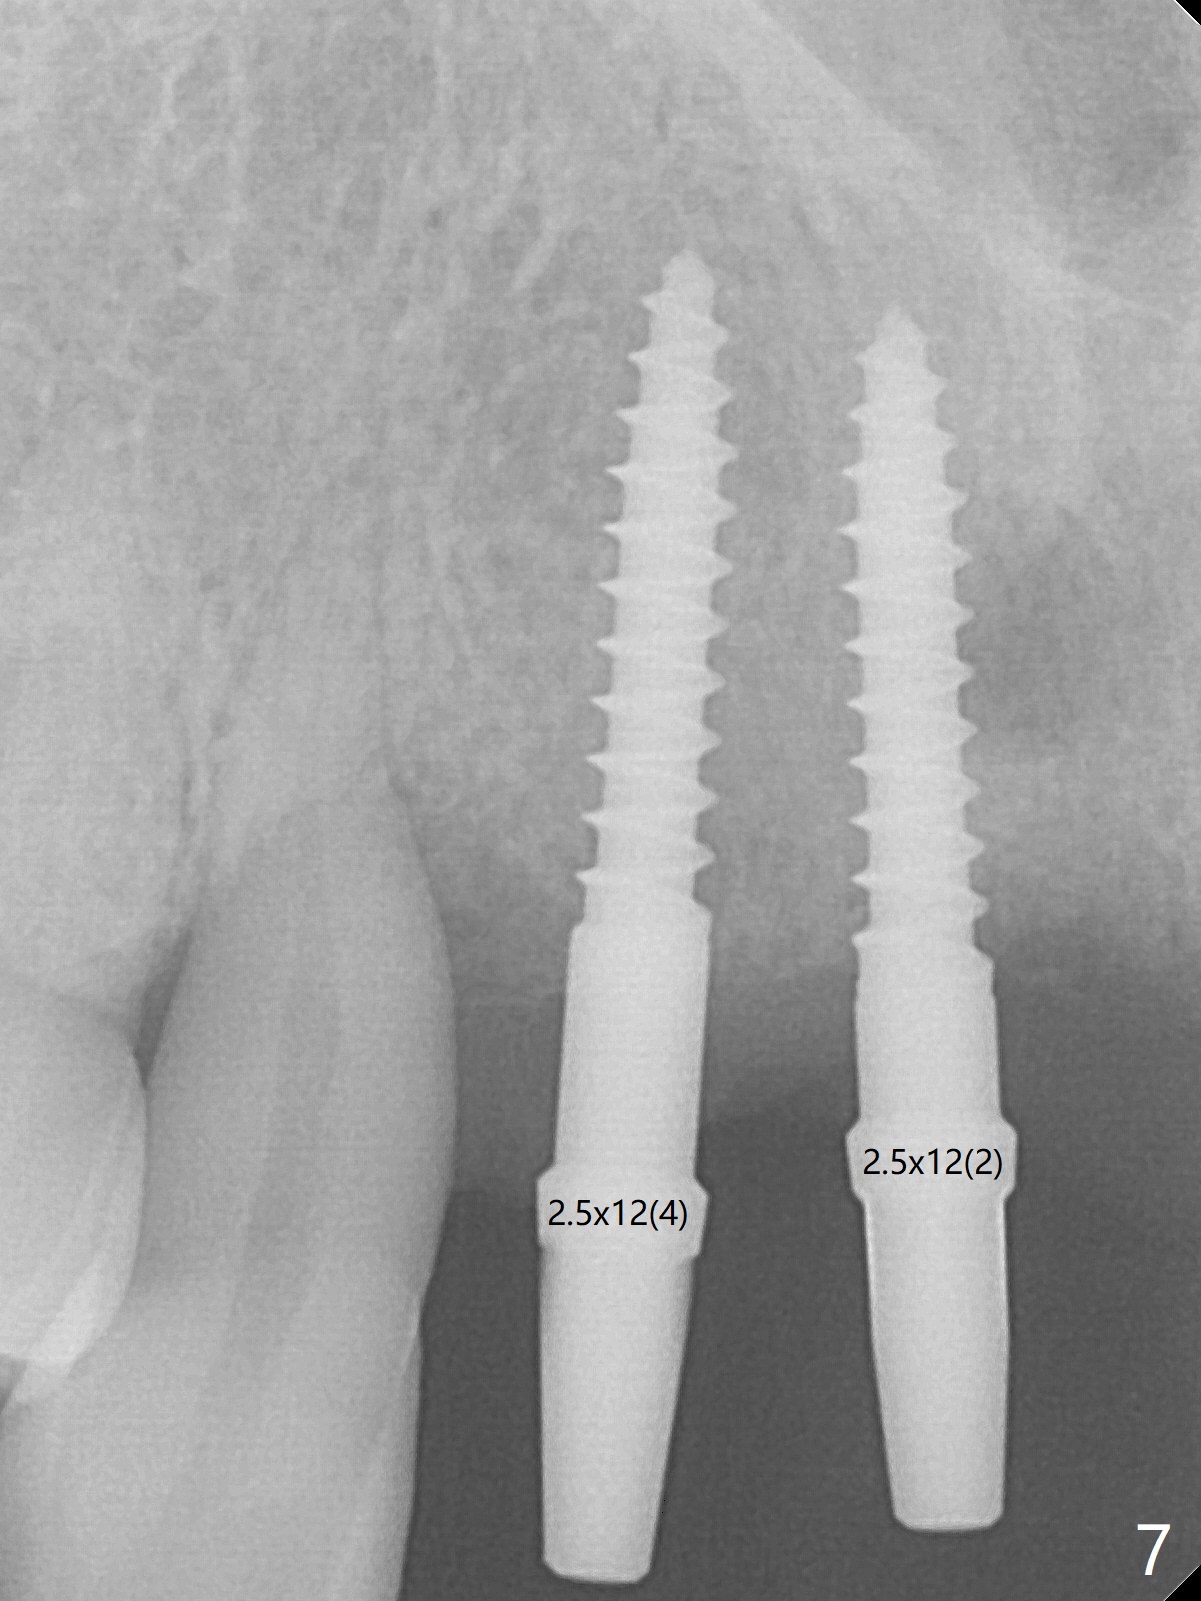

Although the ridge of the maxillary anterior ridge looks moderate in width (Fig.1), the bone is ~4 mm buccopalatally. Suction down surgical stent (Fig.2') made from the lab-fabricated provisional (Fig.2) will be used to check the position and trajectory of osteotomies. PAs taken after initial osteotomies (1.2 mm drill) show those at the central incisors tend to be mesial (close to the Incisive Canal *), while those at the lateral incisor sites distal (Fig.3,4). After adjustment, the position and trajectory of the osteotomies are acceptable (Fig.5,6). To reduce the chance of perforating the Incisive Canal (Fig.3,4 *), 2.5 mm 1-piece implants are inserted with >40 Ncm (Fig.7,8). After deep placement of the implants, Vanilla graft is placed at the crest (Fig.9,10 *). An immediate splinted provisional is fabricated from the suction down stent. The gingiva is healthy around the provisional (Fig.11) and the implants (Fig.12,13) 1 month postop. The provisional is adjusted monthly so that the interdental papillae can be elongated. No bone resorption is observed 6 months postop (Fig.14,15). Crowns are cemented 8 months postop (Fig.16-18). The keratinized gingiva appears to have formed the abutments 8 months postop immediately pre-cementation (Fig.19).